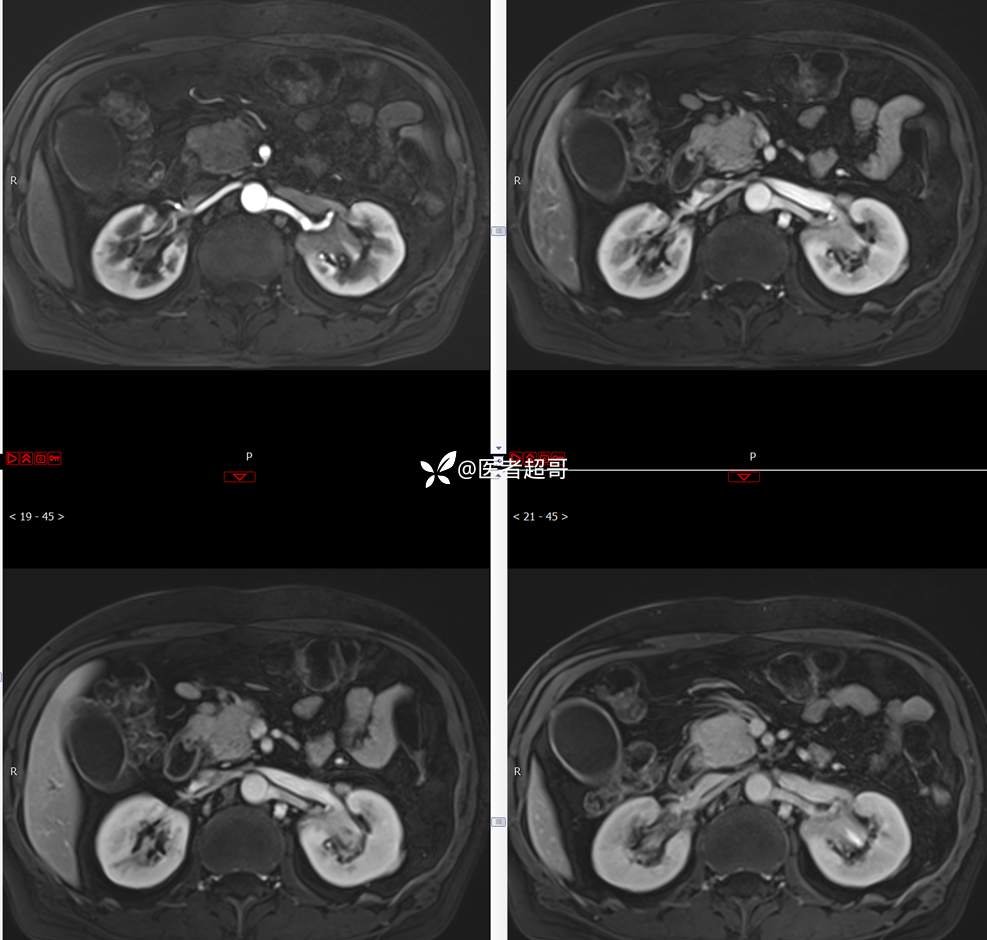

【影诊笔记772】腹痛就诊,发现肾脏病变,CT、MRI齐全,请高诊!

男,63岁 0200825 01

主 诉:间断腹痛15天

现病史:患者15天前无明显原因及诱因出现腹部疼痛不适,呈间断性钝痛,右下腹为著,无尿频、尿急、尿不尽,无发热、寒战,无腹胀。于市中心卫生院住院治疗,超声示:胰头低回声包块,胆系扩张,左肾囊肿,胆囊壁毛糙,胆囊内胆汁淤积。患者为求进一步诊治,遂以“肾盂肿瘤”收入院,患者自发病以来,神志清,精神可,饮食睡眠可,大便无明显异常,近期体重无明显增减。

既往史:既往体健